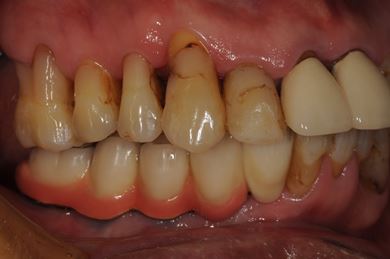

骨再生スピードインプラント治療+遊離歯肉移植

| 主訴 | 入れ歯の部分をインプラントにしたい。 | ||||||||||||||||||||||||||||||||

| 治療方針 | サイナスリフトにより上顎洞を拳上し、インプラント治療を可能にする。 | ||||||||||||||||||||||||||||||||

| 治療内容 | インプラント8本(サイナスリフト、抜歯即日スピードインプラント)、ハイブリッドセラミッククラウン9本、遊離歯肉移植 | ||||||||||||||||||||||||||||||||